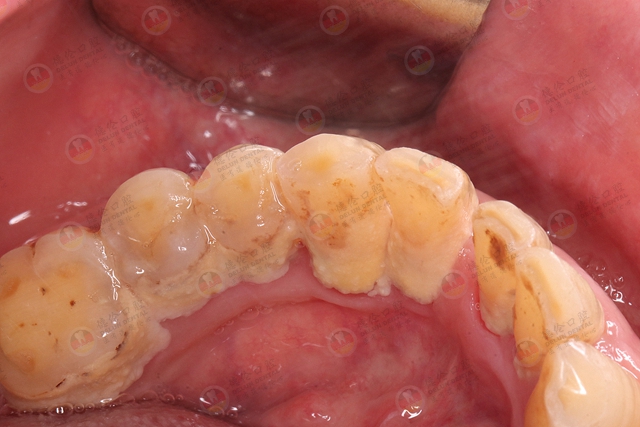

“黑三角”的专业学术名词是——开放性龈楔状隙,指邻间龈乳头不能完全覆盖龈楔状隙而形成的可视三角形间隙。

当牙龈不能完全覆盖两个牙齿的牙颈部与接触点之间的间隙时,肉眼所能看到在两颗牙齿之间出现了一个黑色的、空洞的三角形,俗称为 “黑三角”。

“黑三角”的出现,一个很重要的原因是牙菌斑、牙结石的长期刺激。牙齿没有清洁干净而产生了牙菌斑、牙结石。牙龈血液循环不足,同时受到牙菌斑、牙结石分泌的物质的影响,容易导致牙龈萎缩。

如牙列拥挤,牙齿里的软垢及牙结石就很难清洁干净。牙龈便会一直处于发炎状态,龈乳头就会退缩。